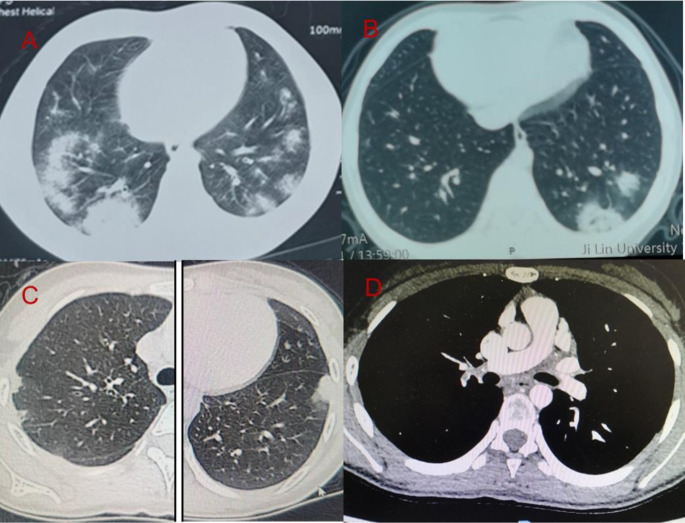

Clinical Characteristics and Outcomes of Pediatric Cases Presenting with Possible Pulmonary Vasculitis Following COVID-19 Infection.

小儿COVID-19感染后可能出现肺血管炎的临床特征和结局